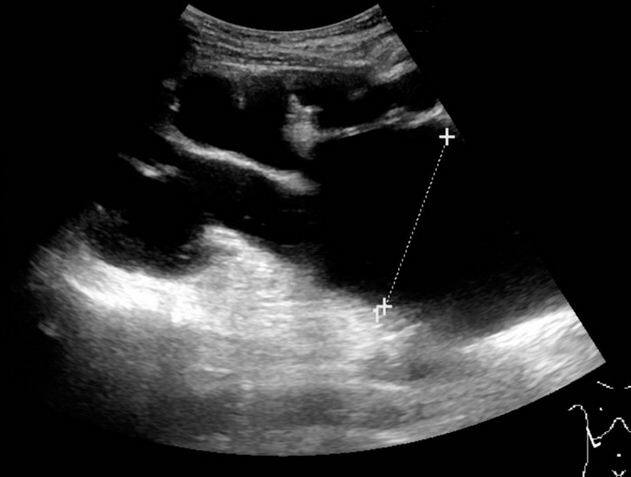

ऑपरेशन से पहले डॉक्टर्स ने इस महिला की दो एमआरआई रिपोर्ट तक चैक नहीं की जिसमें साफ जाहिर था कि महिला की पेल्विक किडनी है वो भी हेल्दी. फोटोः गूगल फ्री इमेज

दरअसल, डॉक्टर्स ने गलती से महिला की हेल्दी किडनी को शरीर में बढ़ने वाला एक कैंसरनुमा ऑर्गन समझा जिसे ऑपरेशन के दौरान निकाल दिया गया. जानिए क्या था पूरा मामला. फोटोः गूगल फ्री इमेज

ऑपरेशन से पहले डॉक्टर्स ने जांचा कि महिला के पेल्विक में कोई मांस जमा है जिसे उन्होंने कैंसर का नाम दे दिया और महिला का इमरजेंसी में ऑपरेशन कर दिया. ऑपरेशन में इस मांस यानि पेल्विक किडनी को निकाल दिया गया. फोटोः गूगल फ्री इमेज